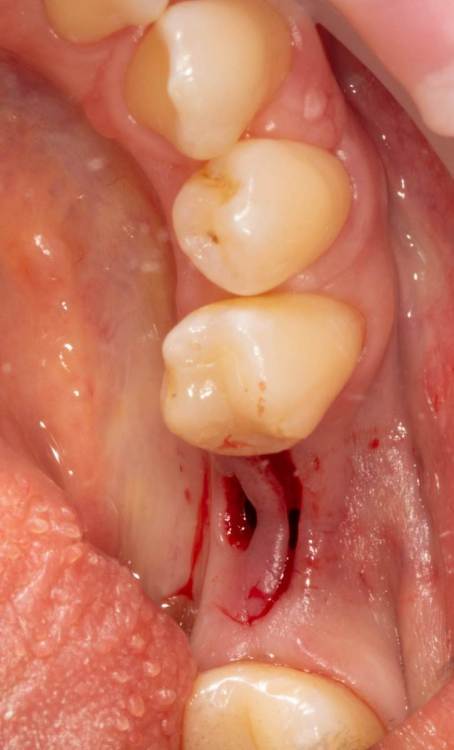

Женька Опубликовано 19 июня, 2023 Поделиться Опубликовано 19 июня, 2023 Здравствуйте, коллеги. Примерно с нового года начал ставить ТЛ имплантаты Дентиум. Что-то под заглушку (не поймал торки, представляете?). Что-то на низких формирвателях. И вот пришла пора протезирования, но отпустить к ортопеду не подготовив десну - не получается. Создал сам себе проблем, сегодня вот исправлял. Получилось неплохо? 3 Ссылка на комментарий

TIGER Опубликовано 20 июня, 2023 Поделиться Опубликовано 20 июня, 2023 Это ж не TL,cубкрестально же.А так я бы длиннее брал ССТ,с захватом соседей Ссылка на комментарий

Женька Опубликовано 20 июня, 2023 Автор Поделиться Опубликовано 20 июня, 2023 @TIGER в смысле это не ТЛ?))) Фото с редукцией не сделал. А то что, шейку погружал - так нужно было. Но это ТЛ. Поверьте) я был на имплантации) Ссылка на комментарий

АнтонТЛТ Опубликовано 20 июня, 2023 Поделиться Опубликовано 20 июня, 2023 Думаю имеется ввиду что имплантат TL установлен по протоколу BL Ссылка на комментарий

Женька Опубликовано 20 июня, 2023 Автор Поделиться Опубликовано 20 июня, 2023 @АнтонТЛТ мы же позиционируем платформу относительно зенита? Есть ли разница тогда, какой имплантат мы выбираем? Вообще весь смысл здесь был заложен в том, что толщина гребня была не очень. Хотелось поставить тонкий имплантат 3.6. Но рисковать тонкой платформой не хотелось, поэтому выбор пал на 4.8 платформу ТЛ и тело имплантата 3.6 1 Ссылка на комментарий

АнтонТЛТ Опубликовано 20 июня, 2023 Поделиться Опубликовано 20 июня, 2023 Конечно относительно зенита, не вдаваясь в подробности, для BL глубже зенита на 3мм, для TL вровень с зенитом. Ссылка на комментарий